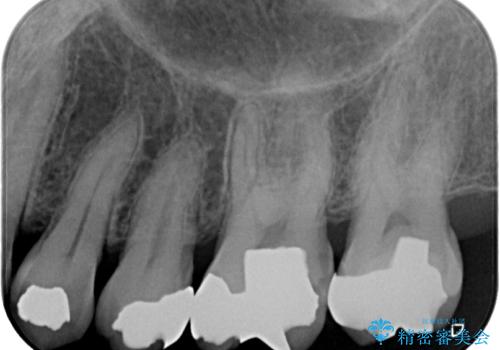

- 奥歯に食べ物がよくはさまるのが気になるとのことで来院された患者様です。

フロスをすると第一大臼歯の部分が引っ掛かり段差になっていることがわかりました。

インレーの範囲が大きいためオールセラミッククランにて補綴することとしました。

前後の歯の詰め物のやり替えも提案しましたが、患者様の希望により第一大臼歯から治療を始めていくこととしました。